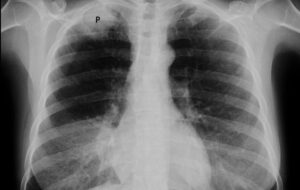

Причины появления коревой пневмонии

Несмотря на массовую вакцинацию в 1960-х годах, корь остается серьезной угрозой. За первые 10 месяцев 2019 года в Европе было зарегистрировано 100000 рабочих мест. случаи кори. По статистике, у каждого четвертого заболевшего развиваются осложнения, требующие стационарного лечения. Одно из таких осложнений — корная пневмония. Общая информация Корь — высококонтагиозное вирусное заболевание, характеризующееся интоксикацией, лихорадкой, специфическими …